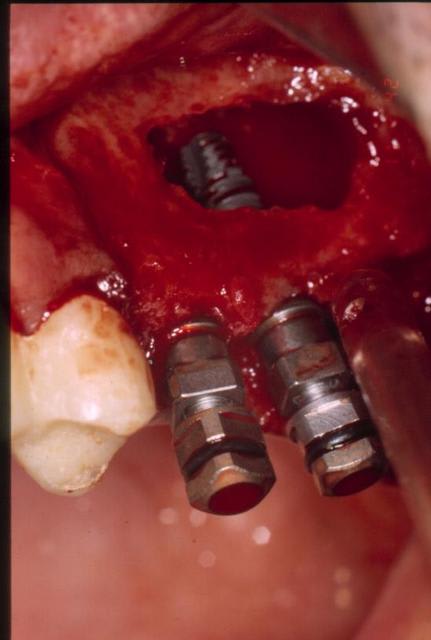

et la suite

Décollement membrane ljuoee - Eugenol

Implants iwsvxa - Eugenol